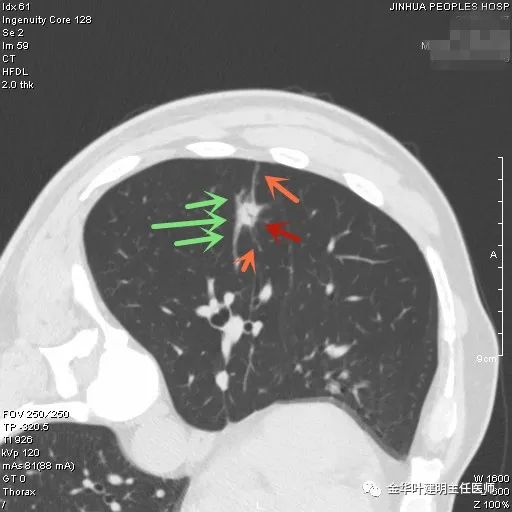

上图示慢性炎结节。我们见其桔色箭头示长毛刺征,绿色箭头示有血管贴边,但进出病灶的血管粗细相对没有什么改变(说明没有被病灶窃取多少血供),整体病灶边缘偏模糊。